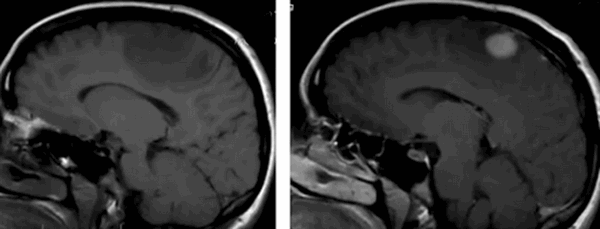

Опухоль мозжечка на МРТ (указана стрелкой)

Опухоли головного мозга долгое время диагностировали исключительно по клиническим признакам, часто слишком поздно. С появлением нейровизуализационных методов стало возможным выявление опасных патологий на ранних этапах их развития. Уже на первых стадиях формирования опухоль головного мозга на МРТ отчетливо видна, а врачи могут планировать дальнейшие действия. Ранняя диагностика увеличивает шансы на выздоровление даже при онкологических заболеваниях.

На рисунке - тазовое предлежание плода, 26 недель. Нормальная анатомия головного мозга

На рисунке - плод, 38 недель. Структурные изменения головного мозга плода не выявлены. Определяется однократное обвитие пуповиной